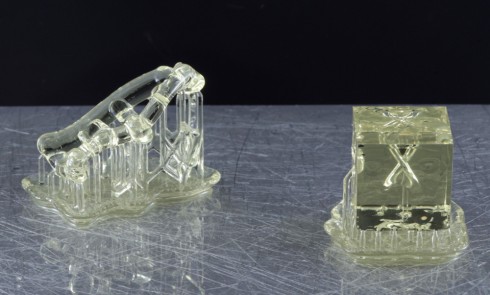

Définitions Degrés de liberté Pour tout objet dans l’espace, il existe six mouvements possibles (trois translations notées : Tx, Ty,...L’impression 3D au service de l’implantologie guidée

La révolution numérique a désormais touché le monde de l’odontologie, lequel connaît une transformation rapide. De nouveaux outils ont permis...L’impression 3D en prothèse amovible complète

Ces dernières années, les avancées technologiques ont permis l’essor de la conception et fabrication assistées par ordinateur (CFAO) et de...La mise en esthétique immédiate 100 % numérique